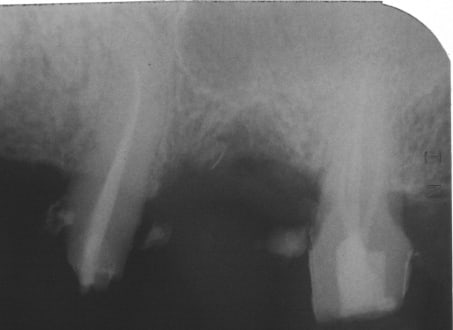

Présentation du cas : extraction de 26 , attente 2 mois cicatrisation, hauteur résiduelle estimé à 5 mm , mauvaise surprise après avoir oté le provisoire, très belle crète bien large mais invaginée en son centre.

Forage au milieu à 3mm + effraction du plancher ,manoeuvre de Walsava OK, bourrage au Gen Oss (0.5cc) , re Walsava, et implant IDCAM 10/5.2 bloqué au maximum .

Tiens jette un coup d'oeil sur la partie mésial de cet implant sans comblement où 3 spires ont été englouties dans la cicatrisation osseuse

> Tiens jette un coup d'oeil sur la partie mésial de cet implant sans comblement

> où 3 spires ont été englouties dans la cicatrisation osseuse

3 spires, cool, mais il en reste quelques une ?

Tu aimes le risque...

La racine mésiale de la 6 ne te fais pas peur ?